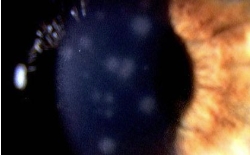

유행성 각결막염 이라는 이름에서도 보시는 것처럼 각막(까만동자)에 까지 염증이 생기면

통증도 심해지고 눈이 부셔서 뜨기도 어렵고 일시적으로 시력도 떨어집니다.

각막에 염증이 생기고 나면 눈병이 낫고 나서도 다음 사진에서처럼 각막혼탁이 남을 수 있구요.

혼탁은 수개월 지속될 수 있습니다.